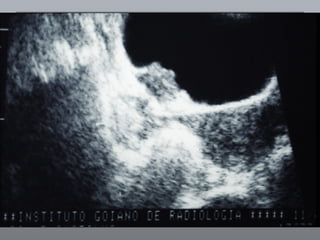

Câncer de Bexiga Estudos de imagens Diagnóstico Ultrassonografia Urografia excretora Estadiamento CT RNM Rx tórax  Cistoscopia + biópsia + biópsias randomizadas

Câncer de BexigaEstudos de imagens Diagnóstico Ultrassonografia Urografia excretora Estadiamento CT RNM Rx tórax Cistoscopia + biópsia + biópsias randomizadas